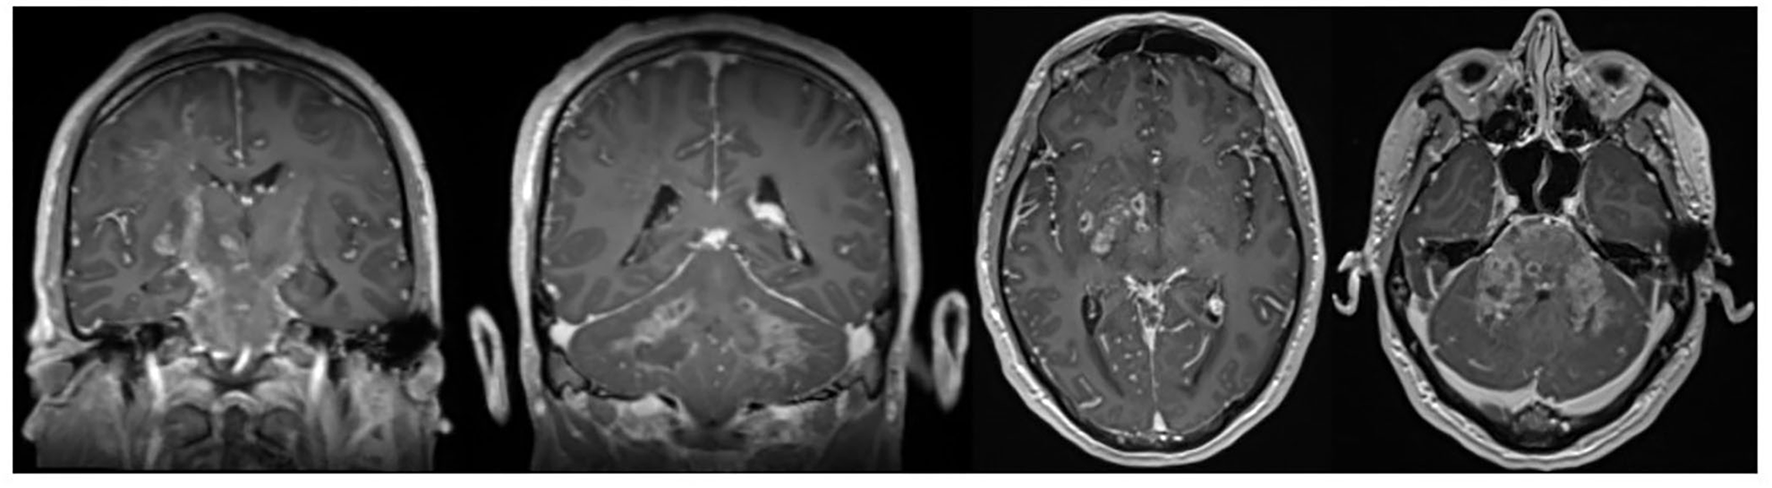

Neuromelioidosis is a rare infection of the nervous system caused by Burkholderia pseudomallei. It accounts for approximately 3% of all melioidosis cases and is statistically associated with much higher morbidity and mortality rate. The transmission of melioidosis is by direct inoculation, inhalation, or ingestion (6). Our case demonstrates an additional mechanism of accessing the CNS via possible entry of the detected pathogen through an exposed mastoid bone defect. Extensive involvement of the brainstem in MRI imaging is common. This could be observed in our case, whose brain-MRI revealed bihemispheric distinctly right-sided accentuated FLAIR hyperintensities as well as rim-enhancing microabscesses spreading along white matter tracts predominantly in corticospinal tracts and cerebral peduncles (Figure 1). Bearing this typical pattern in mind, the rare disease might get diagnosed more often, and initiating therapy in early phases might save patients from persistent disability and death. However, whether the initial immunosuppressant therapy in our case was beneficial by limiting CNS immunoreaction or detrimental by weakening the antimicrobial response remains speculative. An additional frequent radiological feature of neuromelioidosis is thickening of trigeminal nerves, which could also be observed in the brain MRI scans of our patient. This radiological finding may contribute to the identification of the pathogen's entry mechanisms into the CNS potentially through direct axonal transport in cranial nerves (7). Our patient provided a diagnostic predicament as the initial clinical presentation, MRI and, negative cultures delayed the identification of the pathogen and thus the early initiation of appropriate antibiotic treatment. We present the first case of neuromelioidosis in Europe with a severe neurological outcome.

Figure 1. Axial and coronal contrast-enhanced T1-weighted images showing typical rim-enhancing microabscesses spreading along white matter tracts.

Neuromelioidosis presentation can mimic other inflammatory or infectious conditions. Bearing the typical MRI pattern with typical rim-enhancing microabscesses spreading along white mater tracts in mind, this rare disease might get diagnosed more often, and initiating therapy in early phases might save patients from persistent disability and death.